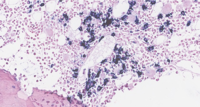

CD138+ plasma cells rimming a lymphoid aggregate (40x magnification).